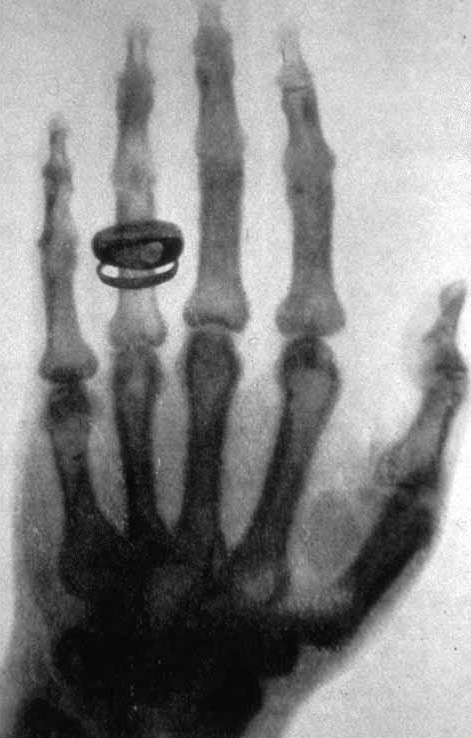

וילהלם רנטגן גילה את קרני X ב־1895. הצילום הראשון היה ידה של אשתו עם טבעת על האצבע. ב־1901 הוא זכה בפרס נובל לפיזיקה. בהתחלה לא הבינו שיש פוטנציאל לנזק, ואנשים נחשפו לקרינה בצורה חופשית. ב־1904 כבר נמצא תיעוד ראשון של אדם שנפטר מנזקי הקרינה.

• מתכת - הכי לבן (למשל טבעת או שתל)

הערה נוספת (דור): בתמונה הראשונה הצבעים דווקא היו הפוכים, נראה שהסטנרט היום הוא ששחור זה אוויר ולבן זה עצם, אבל בתמונה המקורית היד דווקא הייתה שחורה והרקע לבן.

X-ray by Röntgen of Albert von Kölliker's hand